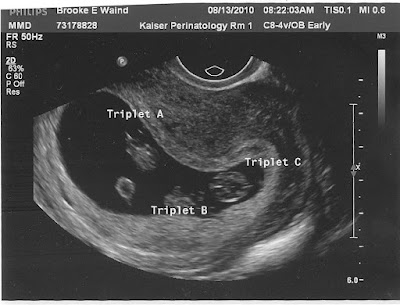

Identical Trips!

We had our 9 week Ultrasound on Friday along with our 1st Perinatology appointment. We were once again shocked lying on the exam table when they told us we are carrying identical triplets!! Now that is some crazy odds, some say anywhere between 1 in 100,000 and 1 in 2oo Million! Why such the widespread? I have no idea, all I know is that I guess we beat the odds. We are asking for lots of prayers during the next 20+ weeks as we among the very rare that are carrying all 3 with only 1 placenta. To get technical they call it Monochorionic Triamniotic identical triplets. Now that's a mouthful! It is going to probably be a roller coaster journey but we feel that we have the strength and support from many loved ones to make it through and welcome 3 new babes to our family. I am secretly (well, not so secretly...who am I kidding!) hoping for girls, but in all honesty we will be blessed with boys or girls!!